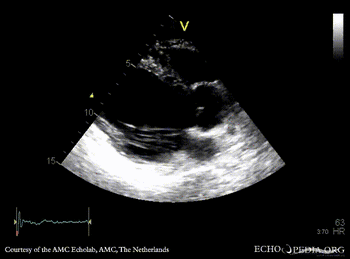

Infarction of posterior and inferior wall

A4CH: akinesia of inferoseptal wall A2CH: akinesia of inferior wall